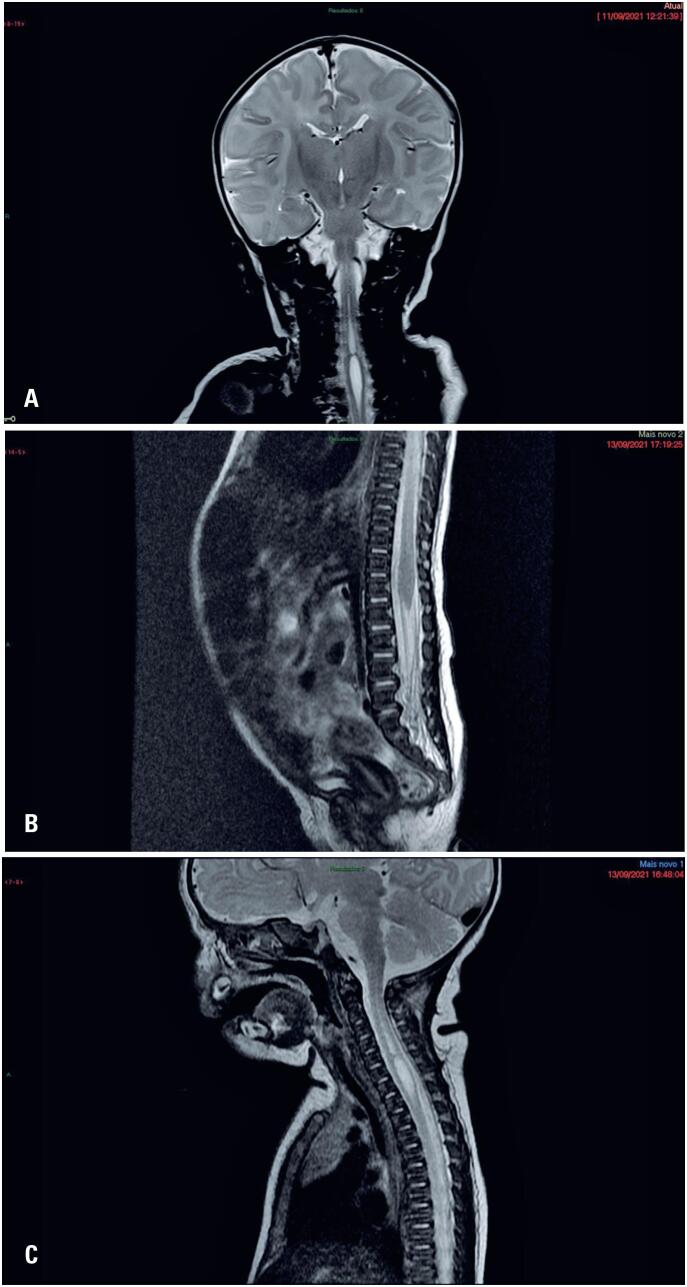

背景:莫比乌斯综合征是一种由于脑神经VI和VII的瘫痪而导致面部模仿能力丧失的遗传性疾病。脊髓空洞症的特点是脊髓中央管扩张,通常无症状。这两种疾病都是通过影像学检查诊断的。我院产房收治一新生儿,体格检查无面部动作。一位专家证实,这种情况是莫比乌斯综合症。磁共振成像进一步研究表明脊髓空洞与莫比乌斯综合征有关。鉴于脊髓空洞症是一种无声的脊髓病,可能对患者未来的健康产生影响,建议在诊断莫比乌斯综合征时仔细分析。迄今为止,很少有类似的病例报告。需要进一步的研究来确定这两种情况之间的实际联系。由于脊髓空洞症的诊断通常是在检查其他疾病时做出的,就像在这项研究中一样,因此对大脑的神经学检查应该扩大到包括脊髓,以证实是否存在共存的疾病。

Background: Moebius Syndrome is a genetic condition that results in inability for facial mimicry due to palsy of cranial nerves VI and VII. Syringomyelia is characterized by a dilation of the central canal in the spinal cord, and is generally asymptomatic. Both disorders are diagnosed using imaging tests. A newborn with no facial movements upon physical examination was admitted to the delivery room of our hospital. A specialist confirmed the condition to be Moebius Syndrome. Further investigation using magnetic resonance imaging indicated that syringomyelia was associated with Moebius Syndrome. Given that syringomyelia is a silent myelopathy with a possible impact on the future health of the patient, careful analysis is recommended when diagnosing Moebius Syndrome. Few similar cases have been reported to date. Further studies are warranted to determine the actual association between these two conditions. Since syringomyelia diagnoses are often made when testing for other conditions, as in this study, neurological examinations of the brain should be expanded to include the spinal cord, in order to verify the presence of coexisting disorders.